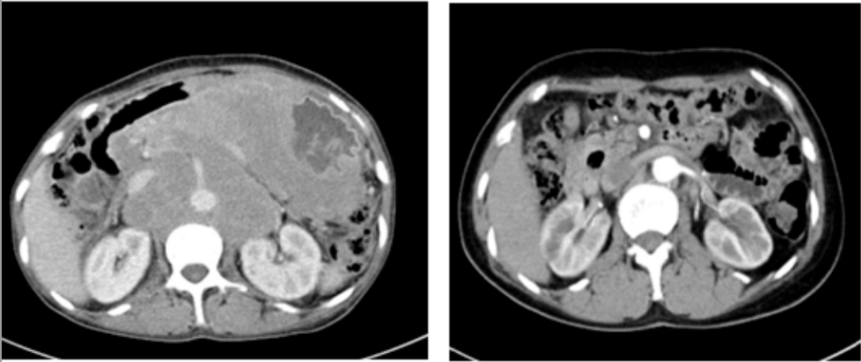

兩年前,張阿姨(化名)的生活被一場突如其來的疾病打亂。持續(xù)地惡心、嘔吐,整整一個月幾乎未進食。在家人的陪伴下,來到國文醫(yī)院進行全面檢查。胃鏡結(jié)果和腹部CT帶來了一個沉重的消息:胃部彌漫大B細胞淋巴瘤,并且已形成一個直徑約10厘米的巨大包塊。這不僅僅是一個腫瘤,更是一枚“不定時炸彈”。因為淋巴瘤的侵犯,張阿姨的胃壁已經(jīng)形成了巨大潰瘍,隨時可能引發(fā)消化道大出血或穿孔,性命危在旦夕。

精密的策略迎來了勝利的曙光,四周期治療后復查胃鏡,原有的巨大潰瘍已完全消失。腫瘤得到有效控制,穿孔風險解除!在此基礎上,后續(xù)的四個周期治療調(diào)整為標準的R-CHOP方案,乘勝追擊,力求徹底清除病灶。

歷經(jīng)八個周期的規(guī)范化療,最終的評估結(jié)果讓所有人歡欣鼓舞:張阿姨的病情在影像學檢查上顯示腫瘤已消失。